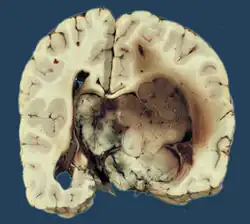

Das Plexus-choroideus-Papillom, kurz Plexuspapillom, ist ein seltener gutartiger Hirntumor, der von der Deckschicht (Epithel) des Adergeflechts (Plexus choroideus) ausgeht. Plexuspapillome sind seltene Tumoren, die nur etwa 0,5 % aller Hirntumoren ausmachen. Ganz überwiegend sind Kinder und Jugendliche betroffen.[1] Das Plexuspapillom führt zu einer Erhöhung des Hirndrucks mit Kopfschmerz, Übelkeit und Erbrechen. Die Diagnose wird durch eine Magnetresonanztomographie gestellt. Nach operativer Entfernung ist die Heilungsaussicht sehr günstig, weswegen der Tumor nach der WHO-Klassifikation der Tumoren des zentralen Nervensystems als Grad 1 eingestuft wird.

Histologie

Das feingewebliche Bild ähnelt mit Ausbildung papillärer Strukturen weitgehend dem des normalen Plexus choroideus. Tumoren, die atypische histologische Eigenschaften (insbesondere eine erhöhte mitotische Aktivität) aufweisen, werden als atypisches Plexuspapillom bezeichnet.[5]

In der Kernspintomographie stellen sich Plexuspapillome recht charakteristisch als intensiv homogen Kontrastmittel aufnehmende, in den Hirnventrikeln gelegene Masse mit blumenkohlartiger Form dar. Bei Kindern und Jugendlichen sind vor allem die Seitenventrikel betroffen, bei Erwachsenen gleichermaßen der vierte Ventrikel. Selten können Plexuspapillome auch im dritten Ventrikel oder ganz außerhalb des Ventrikelsystems liegen.[1][8]